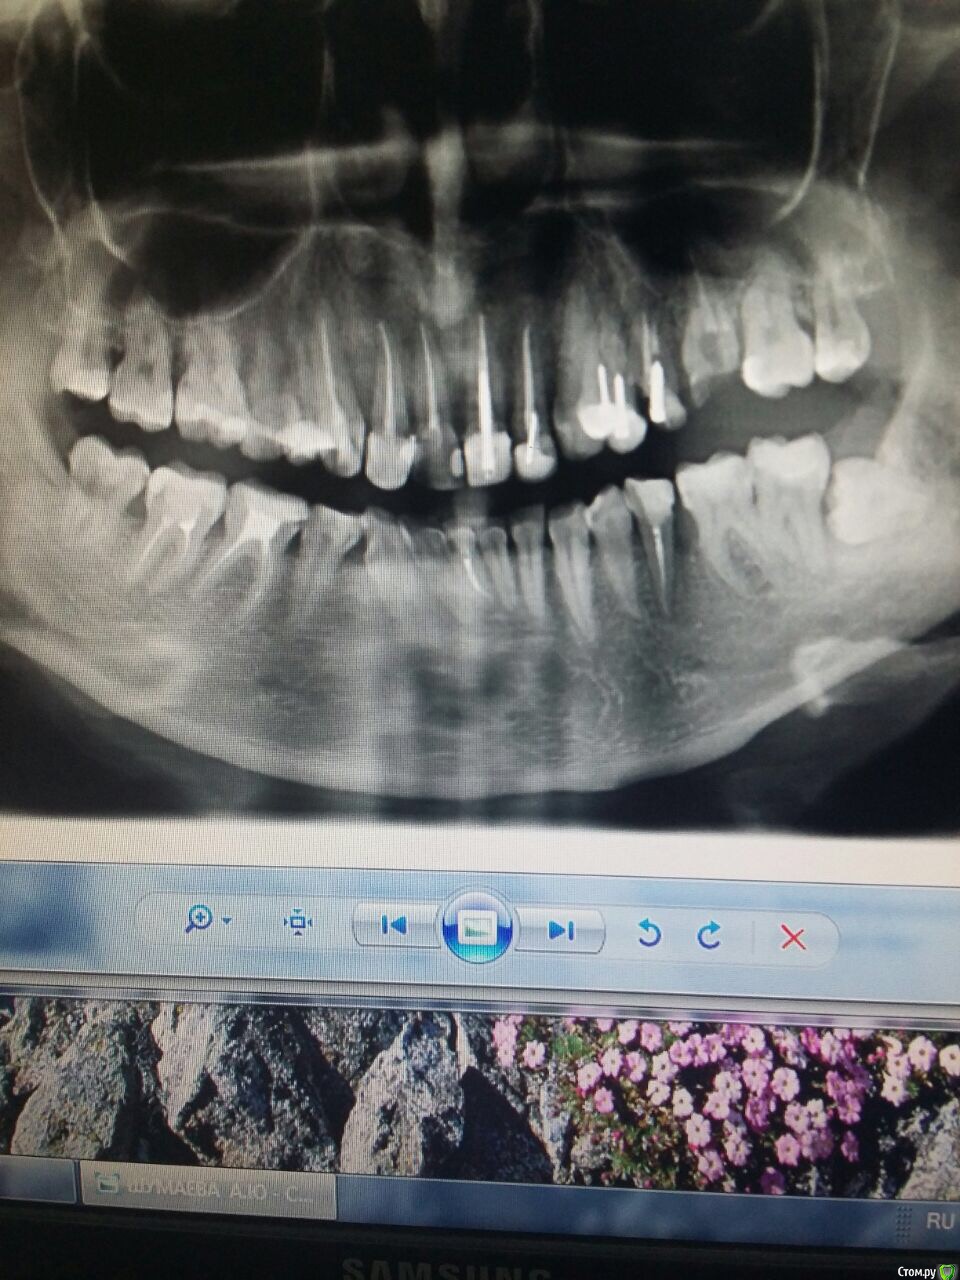

Алена87 Опубликовано 19 декабря, 2017 Поделиться Опубликовано 19 декабря, 2017 Здравствуйте. Воспалились дёсны, пошла к порадонтологу с панорамным снимком. Мне почистили зубы ультразвуком (Безон вроде назывался аппарат)воспаление сняли , но над верхними передними 2-ми все равно ещё присутствует отечностьПародонтолог считает возможным сделать Вектор и то не настаиваетХотя при этом ставит паподонтит средней тяжести Пошла на кослультацию к другому пародонтологу, где сразу было предложено сделать закрытый кюретажХотелось бы узнать , что предпочтительнее в моем случаи ? Вектором только можно обойтись? Ссылка на комментарий

Алена87 Опубликовано 19 декабря, 2017 Автор Поделиться Опубликовано 19 декабря, 2017 (изменено) Панорамный снимок прилагаю Изменено 19 декабря, 2017 пользователем Алена87 Ссылка на комментарий